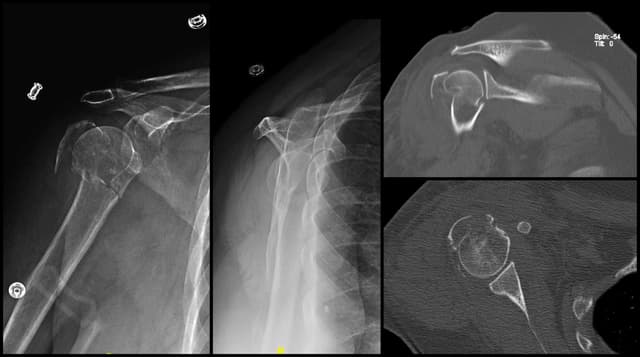

Imaging

Pre-op